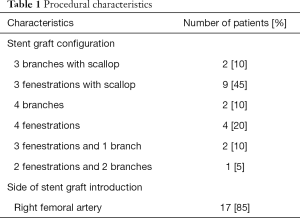

Imaging data of 74 patients were screened for eligibility, of which 43 patients were excluded due to inappropriate CTA resolution and image quality. After CTA examination another 9 patients were excluded due to pre-existing stent grafts. The remaining 22 patients were confirmed eligible for this study. Two patients were excluded during the study because of unsuccessful image registration of the vertebrae. No identifiable reason for failure of image registration could be identified, apart from differences in patient positioning. Additionally, 3 target vessels were excluded due to occlusions of the vessel origin that made it impossible to identify the distal edge of the ostia. A total of 77 target vessels from 20 patients remained available for analysis, consisting of 18 CAs, 20 SMAs, 20 RRAs, and 19 LRAs. Procedural characteristics are represented in Table 1.